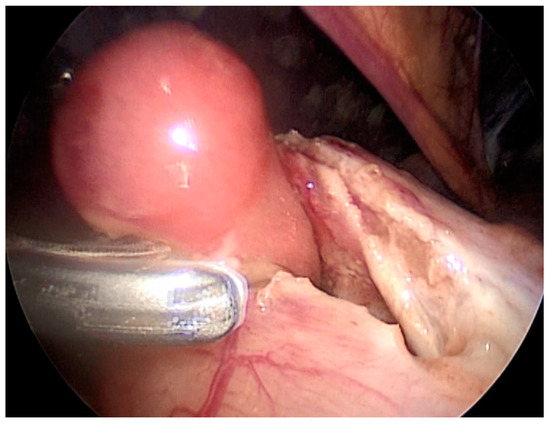

Case number six is a 3-year-old girl who presented with hematemesis and melena. An endoscopy revealed two oval polyps located at the antrum of the stomach with the largest diameters of 1 and 1.5 cm. One of these polyps was bleeding actively and an endoscopic injection hemostasis was conducted. Due to the technical inability, an endoscopic polypectomy was not performed. The next day, a combined laparoscopic–endoscopic “rendezvous” polypectomy was completed. After having polyps endoscopically visualized (Figure 2A), an anterior gastrotomy was performed. A double polypectomy was made using an ultrasonic knife (Figure 2B). The gastric wall was sutured, and the operation was completed with an omentopexy.

Figure 2. Endoscopic visualization of two polyps and laparoscopic polypectomy. (A) After having polyps endoscopically visualized; (B) A double polypectomy was made using an ultrasonic knife.